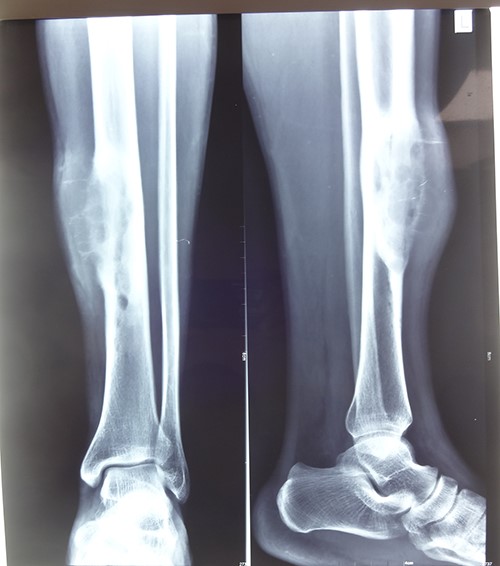

A 33-year-old gentleman presented with slow-growing swelling over the anteromedial aspect of the midshaft of left leg with dull aching pain for 2 years. The swelling was bony hard, 10 cm long and was fixed to the underlying tibia (Fig. 1). Anterior and posterior tibial arteries, sensory and motor functions of the affected legs were intact. Preoperative incisional biopsy report shows multiple epithelial-like cells in a background of fibrous dysplasia, suggestive of adamantinoma. X-ray suggested lytic expansile lesion with multiple septa and sclerotic margins involving the tibia’s diaphysis (Fig. 2). Computed tomography scan showed a cystic expansile lesion with a sclerotic margin obliterating the medullary cavity. Chest X-ray and abdominal ultrasound were normal. The bony defect in the tibia after wide excision of the tumour was 16 cm (Fig. 3) reconstructed with free fibula flap harvested from the opposite leg (Fig. 4). The bone flap was fixed to the tibia with a dynamic compression plate and bicortical screws (Fig. 4). The fibula flap pedicle, peroneal artery and one venae comitantes were anastomosed with the posterior tibial artery and great saphenous vein, respectively. Post-operatively, the flap, flap donor site and recipient’s leg wound healed without complications. Histopathological examination of excised lesion confirmed the diagnosis of classic adamantinoma with margins free of tumour (Fig. 5). After 1 year, there was radiological bone union, evidenced by uninterrupted bony borders between the fibula and recipient tibia bone, obscured osteotomy line at both the junctions and hypertrophy of the transferred fibula as per the bone union criteria by Hsu et al. [3]. The patient started partial weight-bearing in the operated limb after 6 months without any displacement or fracture of the vascularized bone graft. Three years post-surgery follow-up showed good evidence of bony integration and hypertrophy of the bone of the fibula flap, gradually accepting the shape of the tibia without any local recurrence or distant metastasis (Fig. 6). Patient is completely bearing weight on the affected lower limb with good function (Fig. 7).

Roentogram suggestive of a lytic expansible lesion in midtibial lesion.